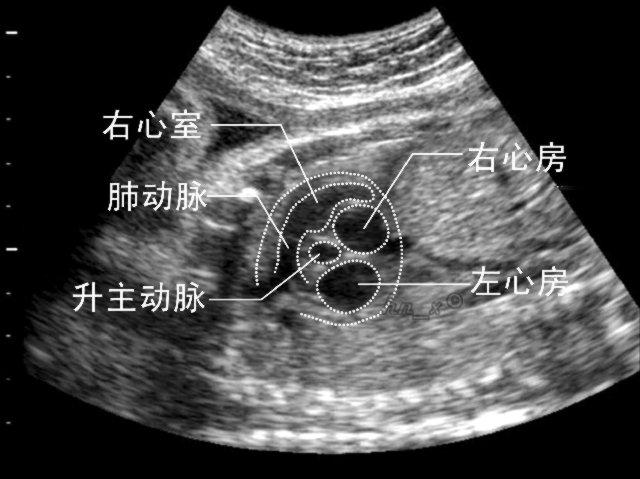

什么是胎心?

胎心是胎儿在子宫内心脏跳动的声音,音色清脆,节律整齐,通过听胎心可了解胎儿健康情况。一般在怀孕7周左右,就可以用B超声设备看到胎儿心跳;怀孕 12 周左右可以用多普勒胎心仪可检测到胎儿心跳;17—20周可以在腹部用一般的听诊器听到胎心。